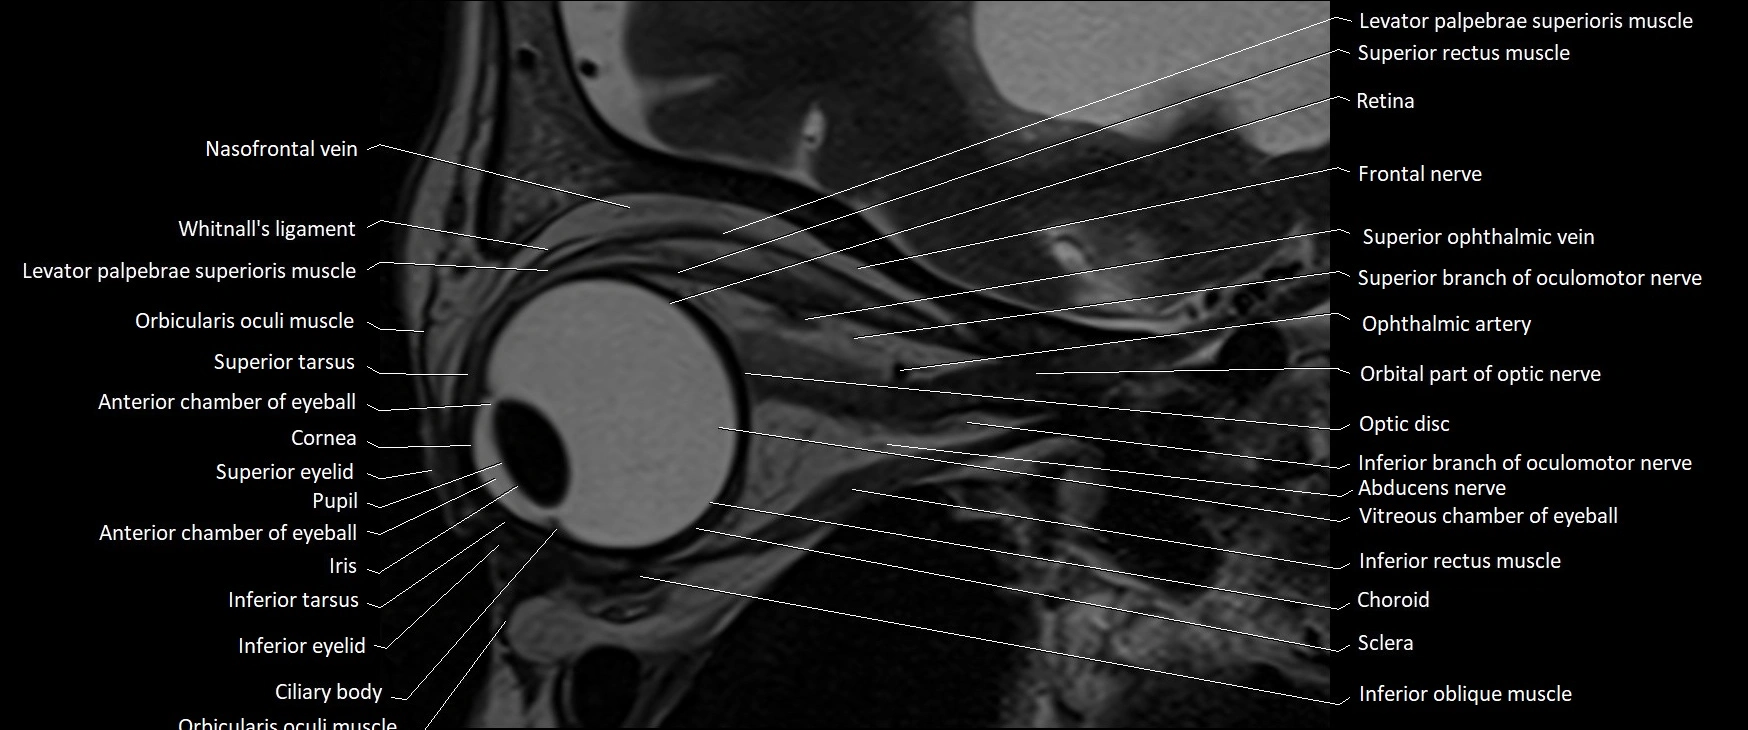

- Anterior chamber of eyeball

- Choroid

- Cornea

- Frontal nerve

- Inferior oblique muscle

- Inferior rectus muscle

- Inferior tarsus

- Iris

- Levator palpebrae superioris muscle

- Nasofrontal vein

- Oculomotor nerve (Superior branch)

- Oculomotor nerve (inferior branch)

- Optic disc

- Orbital part of optic nerve

- Posterior chamber of eyeball

- Pupil

- Retina

- Retrobulbar fat

- Sclera

- Superior eyelid

- Superior ophthalmic vein

- Superior rectus muscle

- Superior tarsus

- Vitreous chamber of eyeball

- Whitnall's ligament

- lens of the eye